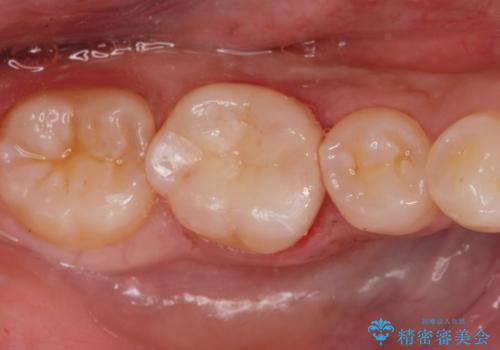

適合が良い詰め物が入りました。

セラミックの材料は虫歯の再発のリスクが低くなります。